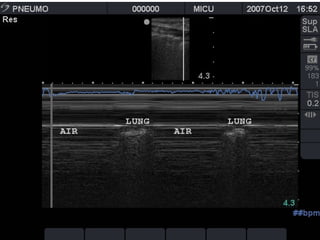

Absent lung sliding

Exaggerated horizontal artifacts

Loss of comet-tail artifacts

Broadening of the pleural line to a band

The key sonographic signs of

Pneumothorax

Absent lung sliding Exaggeratedhorizontal artifacts Loss of comet-tail artifacts Broadening of the pleural line to a band The key sonographic signs of Pneumothorax